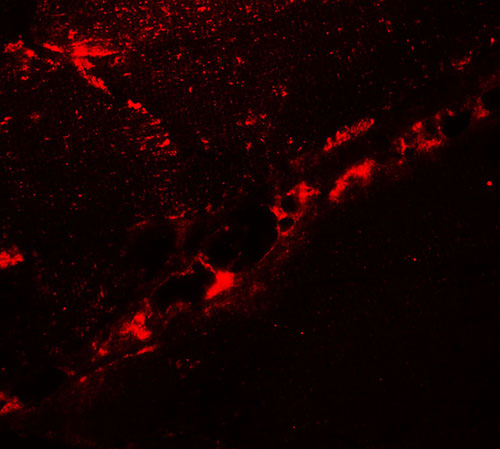

Immunofluorescence of DCNP1 in mouse skeletal muscle tissue with DCNP1 antibody at 20 μg/ml. |